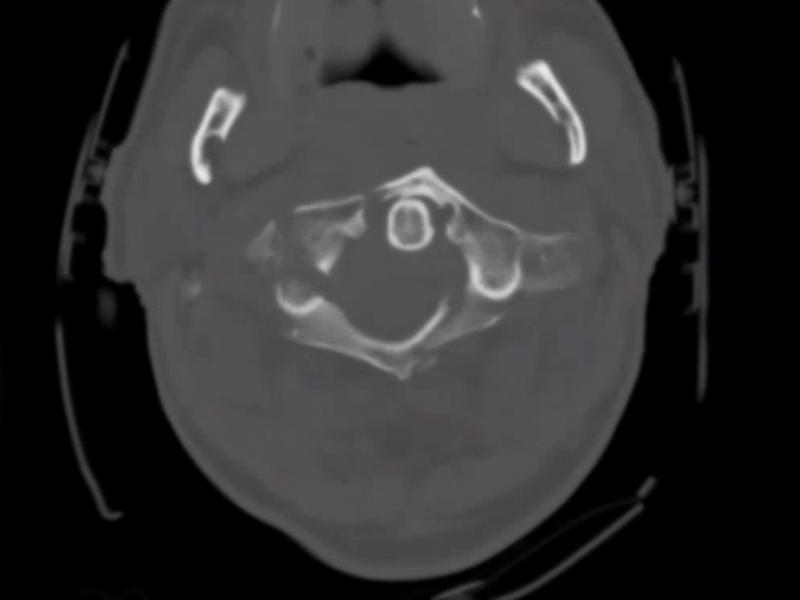

What's the diagnosis? By Dr. Lynn Manganiello

August 14 2019

A 75 yo male presents with neck pain after rollover MVC. He